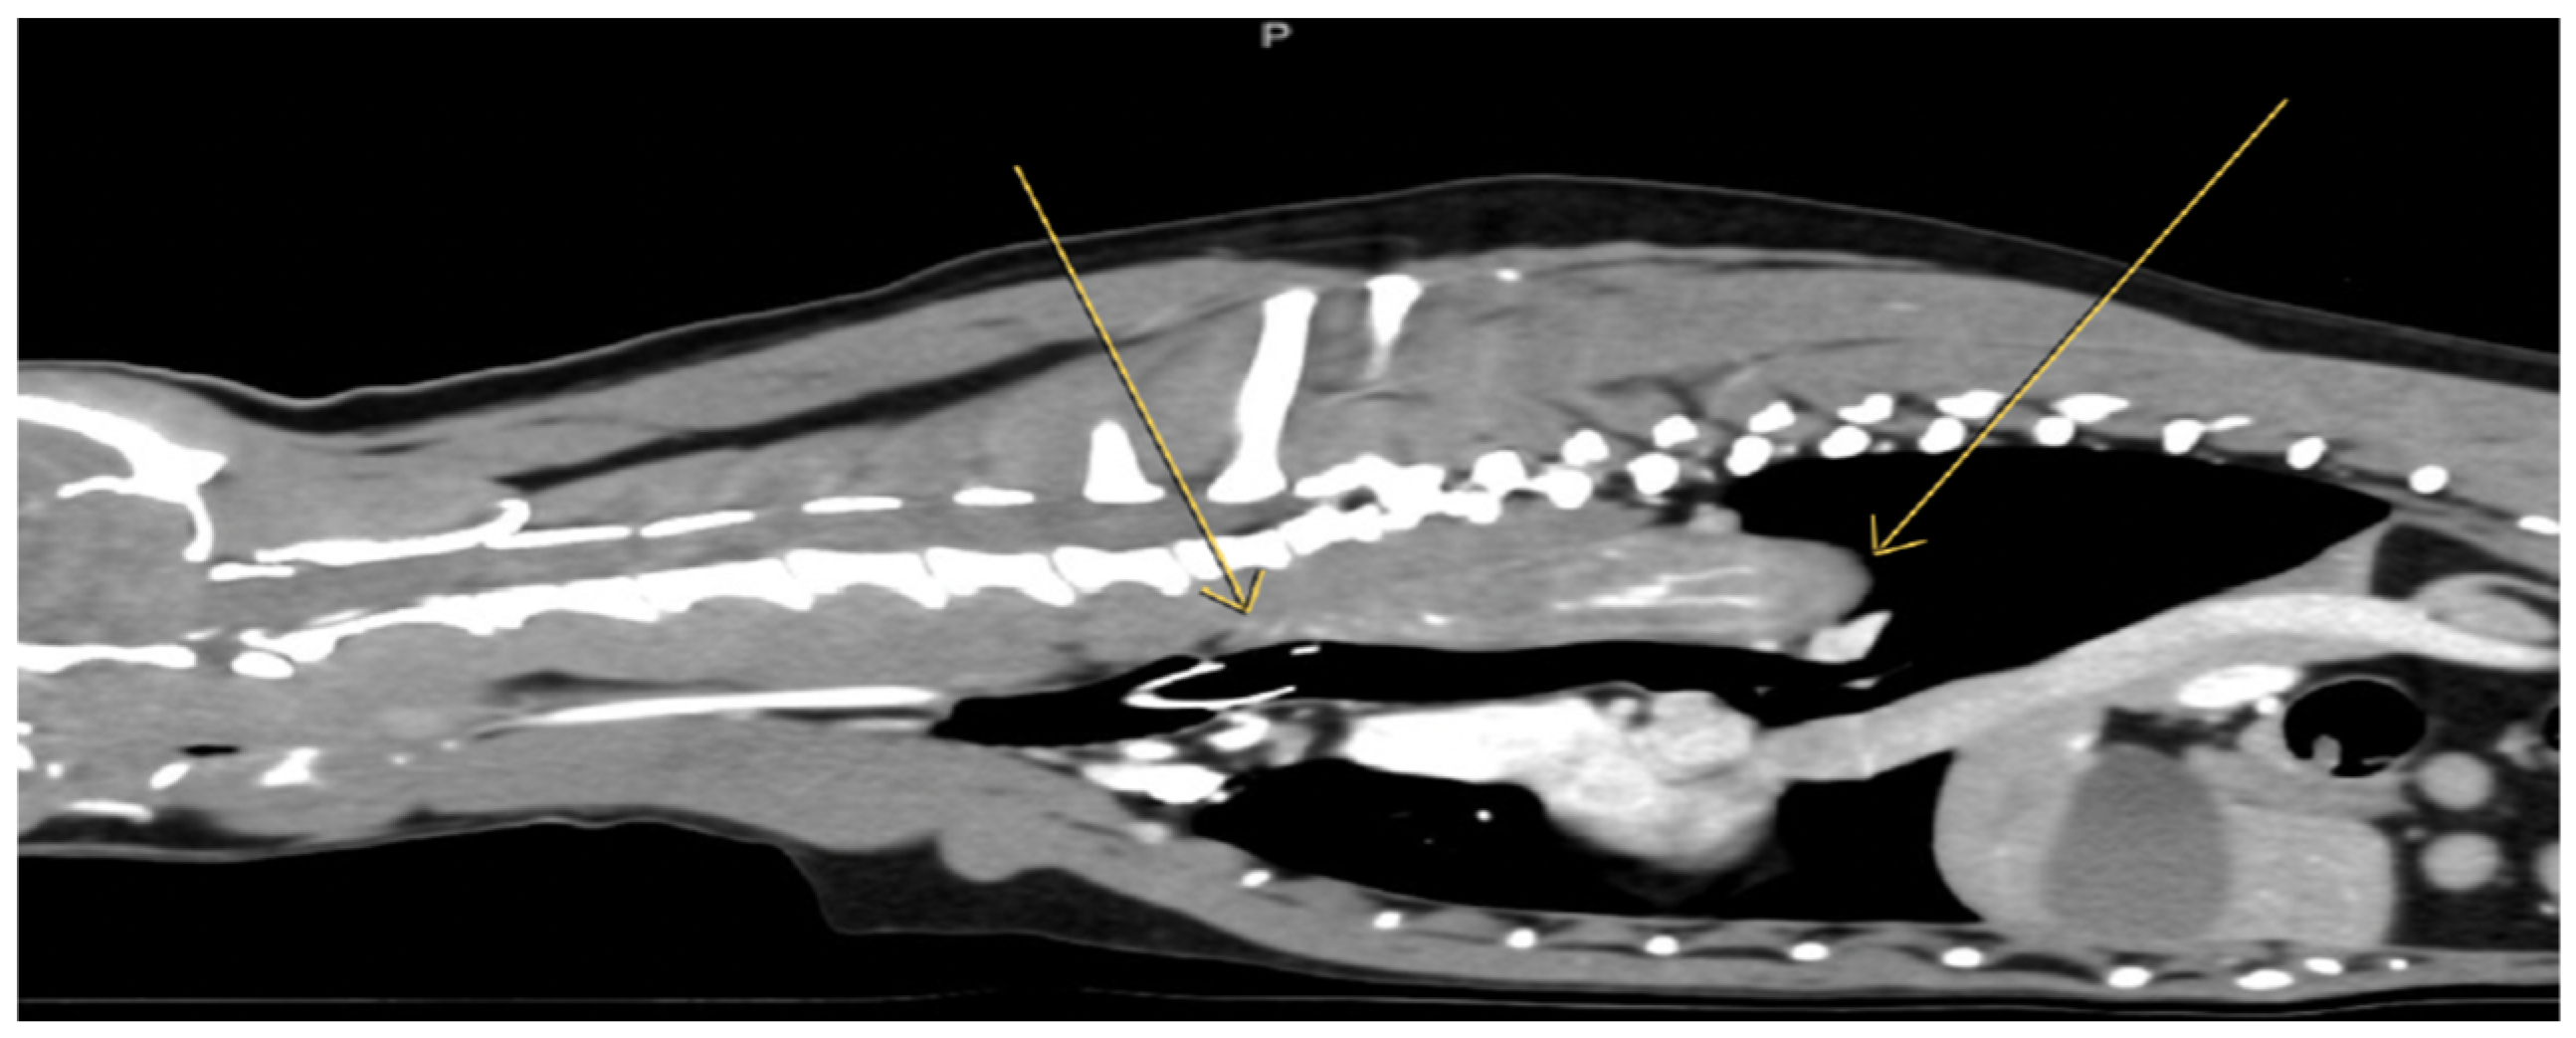

Histopathologic results indicated both proliferative and inflammatory changes suggestive of an inflammatory polyp. These included moderate diffuse chronic lymphocytic, histiocytic, and neutrophilic inflammation, with epithelial hyperplasia, fibroplasia, hemorrhage, and hemosiderin. A dense population of round cells was also noted but interpreted to be part of an inflammatory reaction (Figure 3). A contrast computed tomography (CT) was performed (Figure 4) and surgery was recommended for mass removal.

Figure 4.

Esophageal lesion on sagittal view in computed tomography. The yellow arrows indicate an asymmetrical ductal lesion of the esophagus with spindle-shaped projection in its lumen, soft tissue density, about 7 cm in the longitudinal axis with a high central and peripheral vascularity after intravenous injection of the contrast agent, extending from Th1 to Th7 is noted. A mildly controlled collection of air into the esophagus and mild left axillary lymphadenopathy were detected.